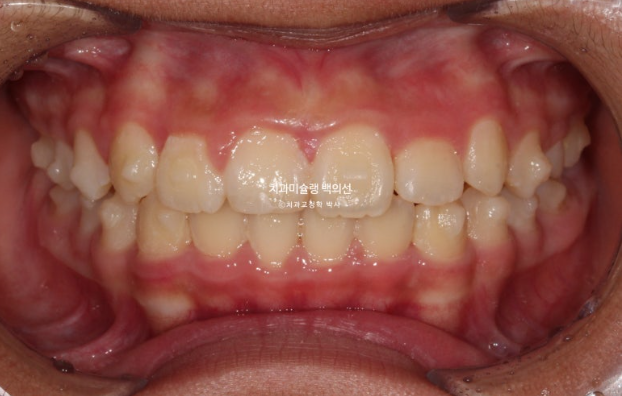

24년 1월 교정치료를 위해 온 만 10세 어린이입니다.

24.02

3년 전에 소아치과에서 앞니 부분교정을 한 적이 있다고 합니다.

그래서 위 앞니에는 중절치 두 개를 잇는 철사유지장치가 붙어있었습니다.

중심선이 약 2mm 어긋나 있고 위 앞니 치축은 한쪽으로 기울어져 있습니다.

앞니가 깊게 물리는 과개교합도 보입니다.

공간부족으로 인한 덧니가 심해 반대교합이 있습니다.